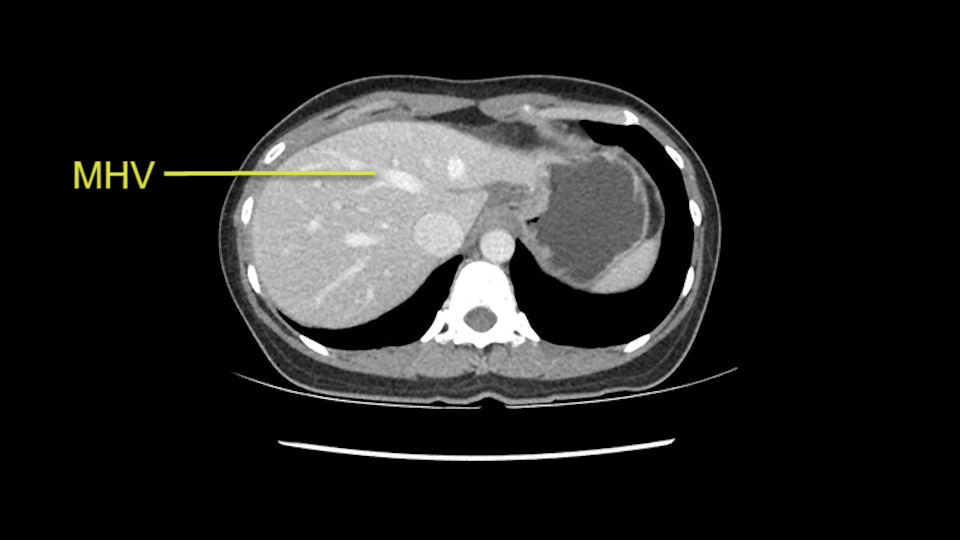

Anatomically, to plan for a left lateral segmentectomy, it’s relatively easy as far as liver surgery goes. I know that I'm going to be looking for the left hepatic vein which will be divided at some point either towards the end at the back near the vena cava or through the middle of the left lateral segment.

Preserve middle hepatic vein

The transection line will be a little more obvious. There’s a little patch of focal fat here in Segment 4b but we’ll describe the transection line probably through the mid portion of Segments 4a and b up to the top. Up at the top, the left hepatic vein can be taken. There’s a Segment 3 vein or the so-called falciform vein it’ll be rudimentary so I think we’ll be able to get around the left hepatic vein and leave the middle [hepatic] vein intact because it’s free of tumor.

Her vein, it looks like a combined middle and left hepatic vein, it may be encircled during the case as a whole common trunk but most probably it will not be a big deal because if it is okay to go with the left lateral resection, the vein or the left hepatic vein can be catched during the intraparenchymal dissection and can be controlled in that side.

The other option of course is to do an anatomical left hepatectomy. In that case, I will start mobilizing of course the left lobe and try to find the ligamentum venosum, take it down and go around the left hepatic vein. I think, importantly in these cases and in this case, as you can see in the venous phase, that’s clearly a moment to stop. Because the left hepatic vein is pretty close to the middle hepatic vein as sometimes it is so you may need to dissect a little bit the parenchyma on top of the left hepatic vein to be able to go around the left hepatic vein safely.